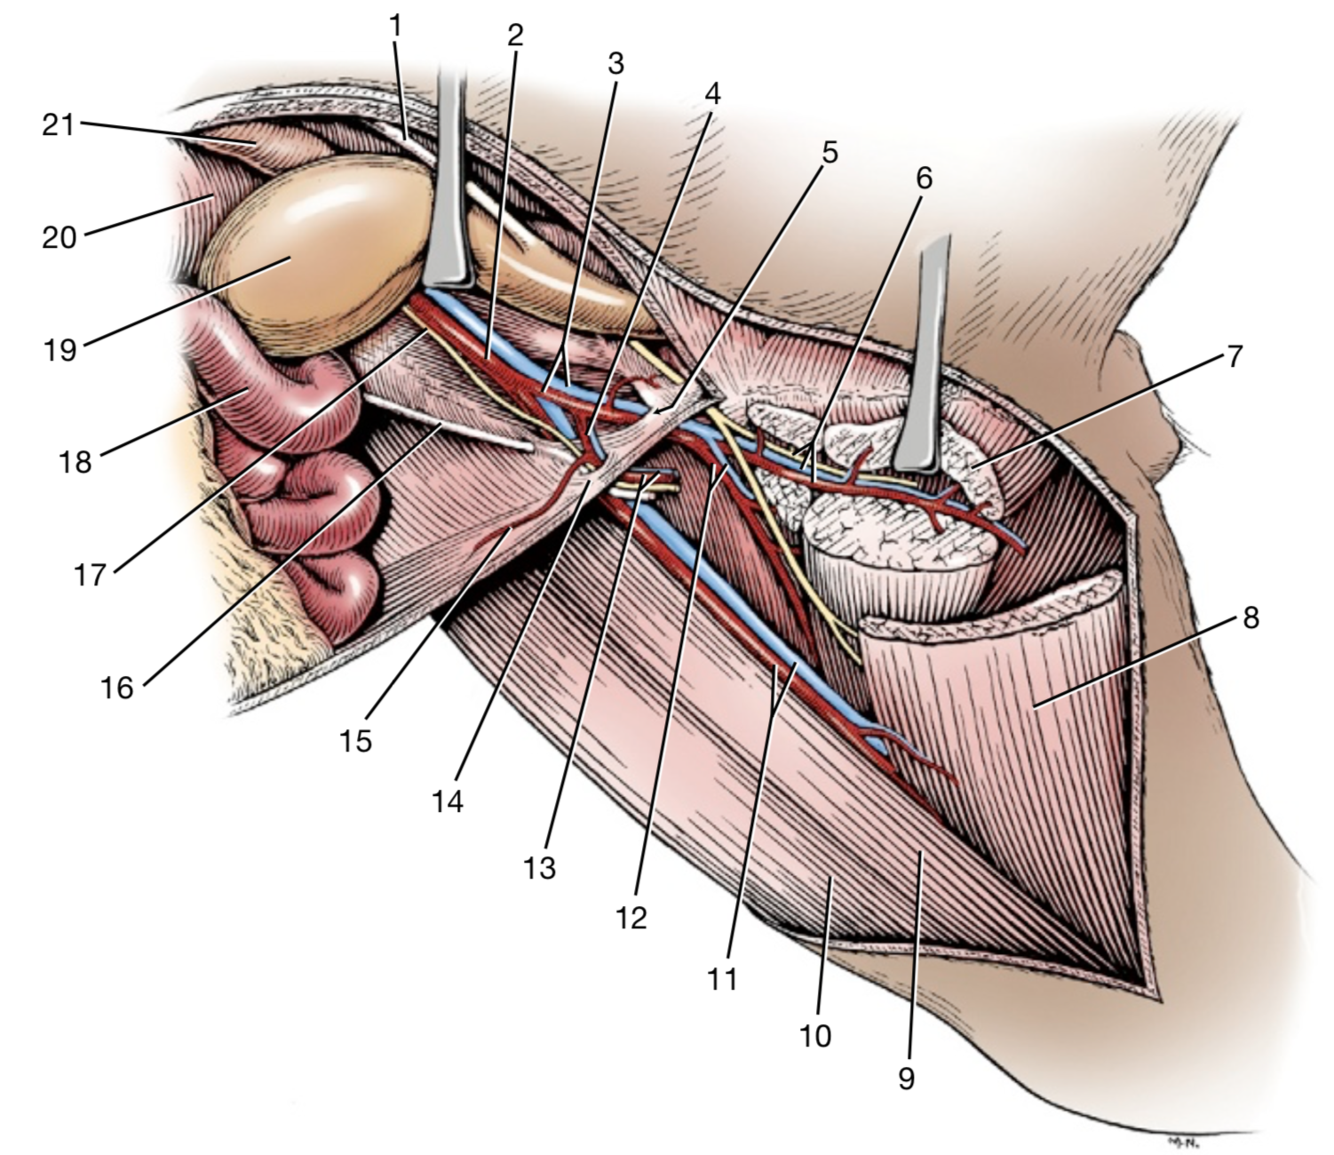

1

Crus mediale

2

Crus laterale

3

A./v. pudenda externa

5

Processus vaginalis

6

M. obliquus internus abdominis

Lig. Inguinalis